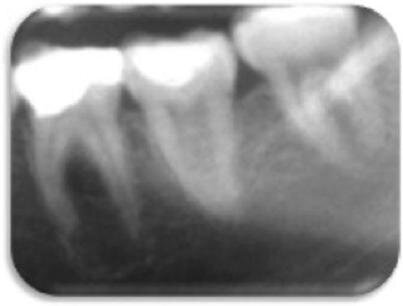

Wykonano końcowe płukanie solą fizjologiczną (3,0 ml), kanał osuszono sterylnymi sączkami, sprawdzanymi na obecność wysięku. Kanały wypełniono ćwiekami gutaperkowymi (2 x F3 i 1 x F4), stosując technikę autodopasowania, pionowego ubicia i uszczelniacz na bazie żywicy epoksydowej (TopSeal, Dentsply), (Ryc. 4 i 5).

Kontrolę radiograficzną oraz weryfikację kliniczną przeprowadzono po 6 miesiącach (Ryc. 6), 1 roku (Ryc. 7), 2 latach (Ryc. 8) i 3 latach (Ryc. 9 i 10). W okresie prowadzonej obserwacji ząb pozostał całkowicie bezobjawowy, zaobserwowano jednocześnie gojenie tkanek okołowierzchołkowych.